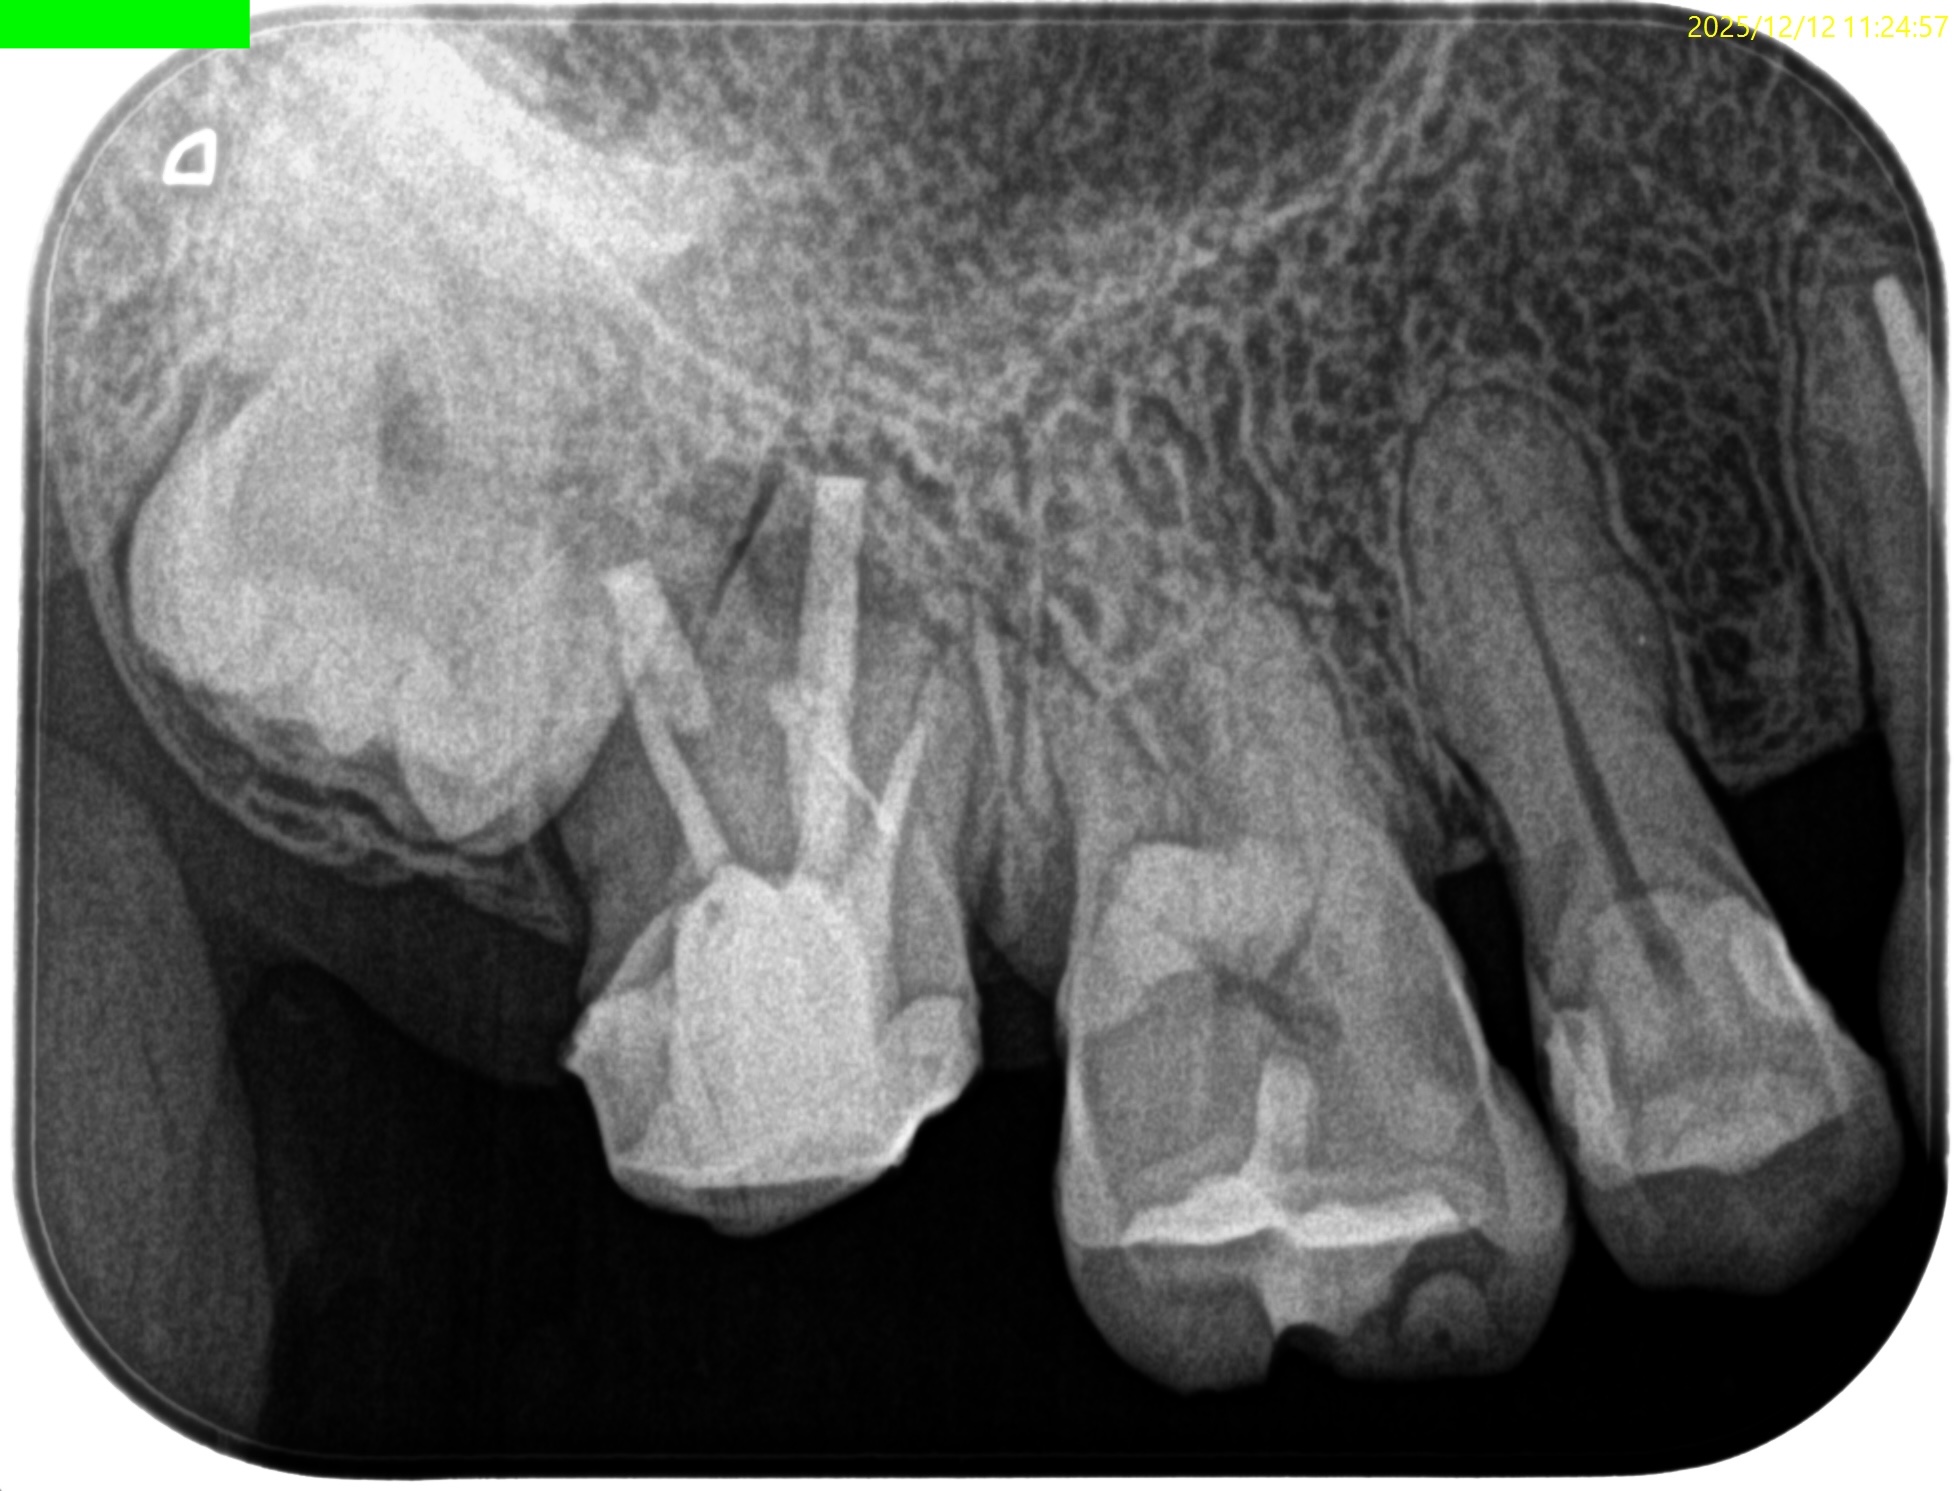

術後にPAを撮影した。

MB

DB

P

問題はないだろう。